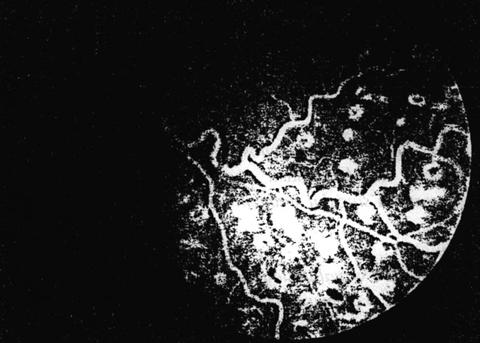

Fig.

12

Fig. 13

Fig. 14